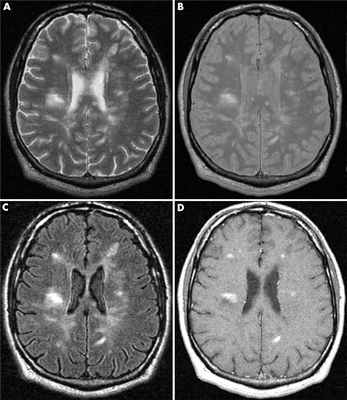

Как распознают рассеянный синдром на снимках? При рассеянном склерозе на снимках заметно характерно типичное распределение очагов в белом веществе головного мозга. Кроме того, для данного диагноза характерно поражение мозолистого тела, дугообразных волокон, височных долей, мозгового ствола, мозжечка и спинного мозга. Такое распределение очагов нехарактерно для иных патологических процессов, поэтому трудностей при постановке диагноза обычно не возникает. При ангиопатии возможны поражения ствола мозга, однако они обычно симметричны и располагаются центрально, в то время как очаги при рассеянном склерозе локализованы по периферии.

В методе магнитно-резонансной томографии, исходя из названия, применяется иная физическая основа. Кратко опишем этот метод. Итак, из школьного курса физики мы знаем, что существует магнитное поле. Оно есть у всех тел в природе: у нашей Земли, у нашего с Вами тела, у каждого атома нашего тела. Поэтому к каждому телу можно пририсовать стрелку, показывающую направление магнитного поля. Если к атому прилагается внешнее магнитное поле, более сильное, чем у атома, то магнитное поле атома стремится выстроиться вдоль внешнего магнитного поля, параллельно ему. Насколько быстро и насколько точно встанет стрелка магнитного поля атома зависит от свойств самого атома: одни атомы выстраиваются быстро и ровно по направлению внешнего поля, другие с отклонением и медленно. В магнитно-резонансном томографе подается мощнейшее магнитное поле, чаще всего его напряженность составляет 1,5 Тл. К примеру, магнитное поле всей Земли составляет 0,00005 Тл. Магнитно-резонансный томограф представляет собой очень большой магнит, в центре которого напряженность магнитного поля наибольшая. Вас кладут на кушетку, затем кушетка начинает двигаться к центру магнита, похожего на трубу. Когда Вы достигаете центра магнита, то начинается процесс исследования. Магнитные поля всех атомов Вашего тела выстраиваются вдоль поля большого магнита (все маленькие стрелки встают параллельно большой стрелке). Затем перепендикулярно к основному полю магнита подается кратковременный импульс другого сильного поля. Это приводит к наклону всех маленьких стрелок атомов Вашего тела – они выстраиваются уже вдоль этого кратковременного, но очень сильного магнитного поля. Грубо говоря, все магнитные оси атомов ложатся на бок. Когда действие импульса заканчивается, магнитные стрелки атомов вновь возвращаются в положение вдоль направления магнитного поля основного магнита (вдоль трубы). Так вот, скорость возврата магнитных осей из положения на боку в вертикальное положение у разных атомов различно. У атомов водорода оно одно, у атомов кислорода другое, у атомов меди третье, у атомов железа четвертое. А так как каждый участок тела, каждый участок головного мозга состоит из разного количества разных атомов, то и возврат атомов к вертикальному положению осей будет от каждого микроскопического участка головного мозга разным. Существует два основных вида изображений: T1-взвешенное и T2-взвешенное. На Т1-взвешенном изображении фиксируется скорость возврата атомов из положения на боку в вертикальное положение. На Т2-взвешенном изображении время удержания атомов в положении на боку после кратковременного перпендикулярного импульса. Компьютерная программа обрабатывает микроскопические участки мозга по этим параметрам и формирует изображение. Участки демиелинизации существенно отличаются по количеству и спектру атомов от здоровой ткани и видны на Т2-взвешенном изображении в виде белых очагов.

Следует упомянуть и про режим FLAIR: построение изображения в этом режиме происходит путем удаления (не учета) молекул воды, что дает более четкую и более полную картину очагов демиелинизации.

Существует несколько видов МРТ-сканирования, которые на «языке» медицинской диагностики называются последовательностями. Чаще всего используются Т1-и Т2-взвешенные последовательности – различие между ними заключается в длительности воздействия радиоволн. Компьютерные программы преобразуют полученные во время сканирования данные в изображение ткани тела в каком-либо сечении. При этом Т1-и Т2-взвешенные изображения не дублируют друг друга, а представляют разную информацию о состоянии структур мозга. Так, на Т1-последовательностях хорошо видны опухоли нервной системы, а Т2-последовательности позволяют визуализировать воспалительные процессы. Специально разработанный режим FLAIR «удаляет» эффект ликвора (жидкости, циркулирующей в полостях мозга) на построение изображений. В последнее время в широкую практику входят новые специфические последовательности МРТ-исследований, направленные на улучшение отображения отдельных структур головного и спинного мозга. Так, режим DIR позволяет детально изучить повреждения в коре головного мозга, толщина которой составляет всего несколько миллиметров. Посредством режима STIR удаётся исключить влияние сигнала от жировой ткани оболочек мозга и позвоночника и получить изображения структур спинного мозга с особенным качеством.

Как МРТ «показывает» рассеянный склероз

В норме ткань мозга отделена от циркулирующей крови посредством так называемого гематоэнцефалического барьера, который представляет собой слой особых клеток, «окутывающих» кровеносные сосуды и не позволяющих жидкости свободно проникать через этот барьер. Кроме того, слой миелина, защищающего волокна нервных клеток, содержит в себе большое количество липидов (жиров), за счёт чего он отталкивает воду. Поэтому содержание воды в нервной ткани в целом невелико и является практически постоянным. Однако при рассеянном склерозе воспалительный процесс повреждает гематоэнцефалический барьер, что позволяет жидкой части крови попадать к нервным клеткам. Также начинает разрушаться и сам слой миелина, что значительно снижает его «водоотталкивающие» свойства. В результате в очагах воспаления в ткани мозга содержится значительно больше воды, чем это должно быть. Именно это повышенное содержание воды отображается на скане МРТ или в виде яркого белого пятна (на Т2- и FLAIR-изображениях) или затемненной области (на Т1-изображениях).